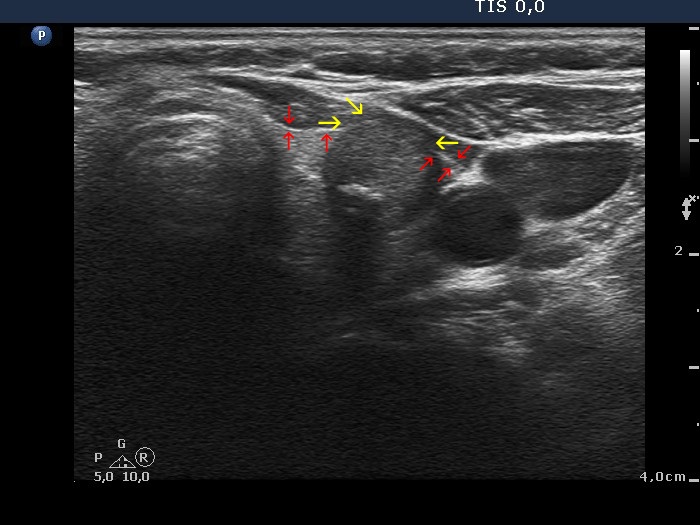

Extrathyroidal spread - case conp 021 (ultrasonographic picture 4b)

Upper part of the left lobe, transverse scan. Red arrows point to those part of the capsule where it is intact. The capsule is completely broken between yellow arrows. This is that part of the nodule where it presents abutment.